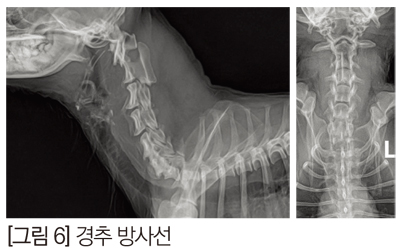

2. Rongeurs

Rongeurs를 이용해 뼈를 조금씩 잘라내면서 척수에 접근할 수 있다. 시간이 더 필요할 수 있고, slot의 형태가 다른 기구를 사용한 것보다 외형상 정갈하지 못할 수는 있지만 bur보다는 더 안전한 접근이라고 볼 수 있다. [그림 6]